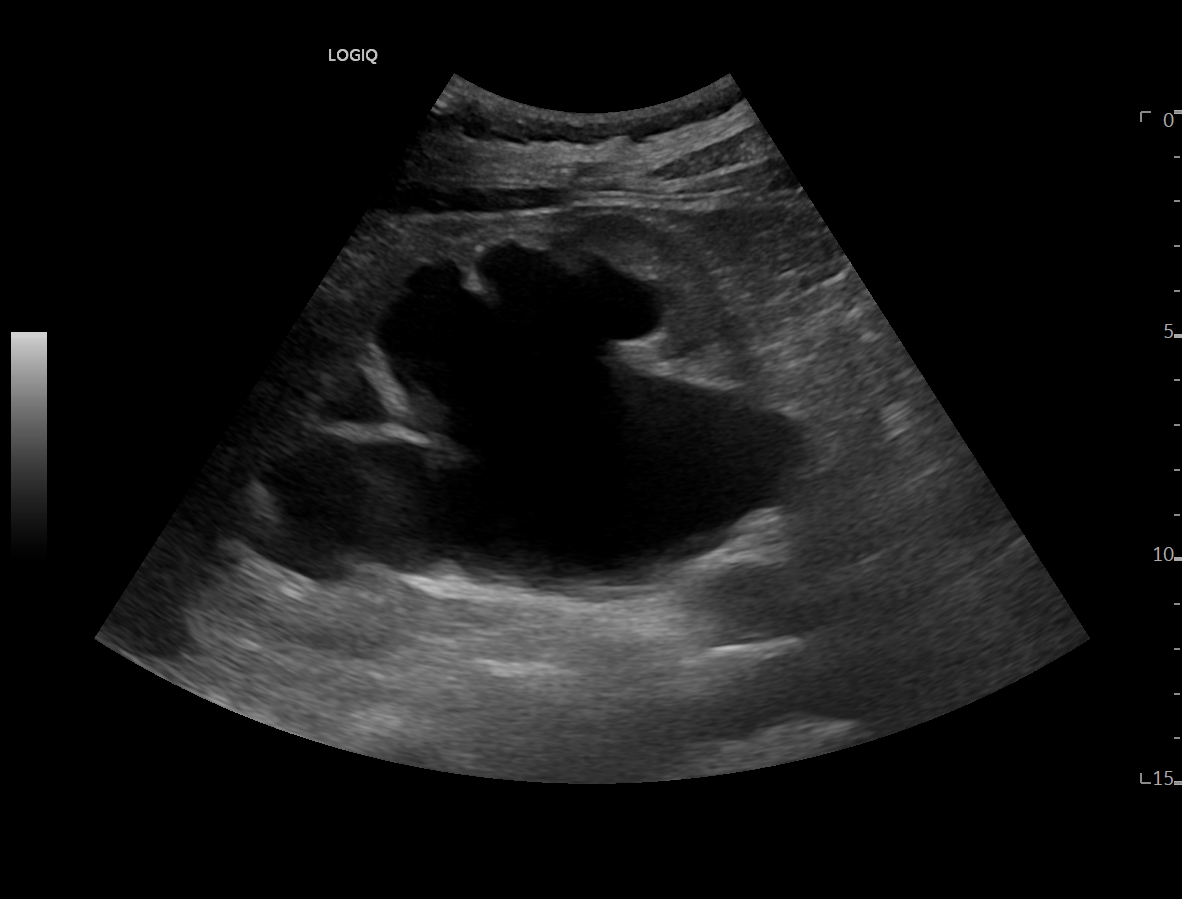

Ya en urgencias hospitalarias, se realiza ecografía clínica donde se aprecia ureterohidronefrosis derecha grado IV con pérdida completa de ecoestructura renal por el incremento del volumen que presenta, no presentando las mismas alteraciones en el lado izquierdo, pudiendo esto indicar una obstrucción completa no resuelta.

La ecografía clínica reglada informa de dilatación de pelvis renal de hasta 5,7 cm con aumento de tamaño renal hasta 13 cm, apreciando litiasis obstructiva de 12 mm en uréter distal a unos 5 cm del meato ureteral derecho.